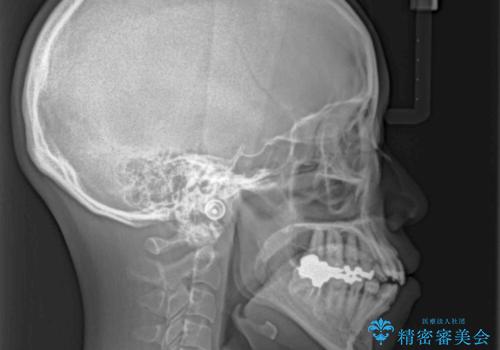

出っ歯と奥歯の欠損 ワイヤー矯正とインプラント治療

- 口元の突出感と奥歯の欠損を気にして来院された患者様です。

口元の突出感改善には、上下左右の第一小臼歯4本を抜歯し、奥歯の欠損部には矯正治療の途中でインプランを埋入していくこととしました。

矯正治療の後半にインプラント埋入を行うことで、トータルの治療期間を短縮することができました。